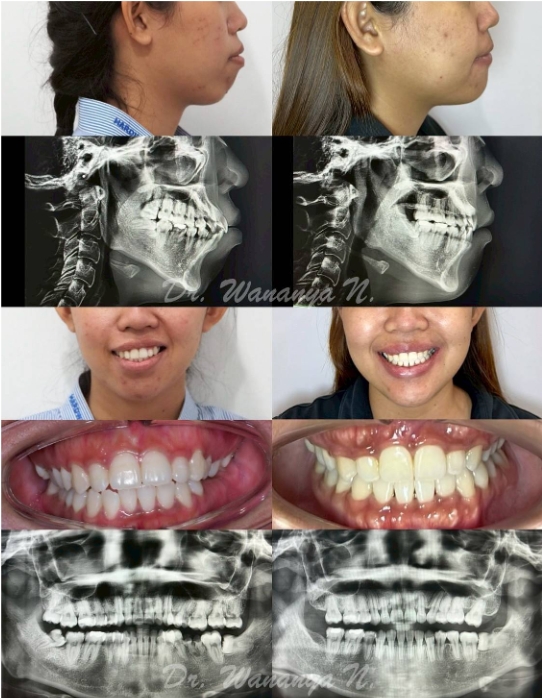

เคส รีวิว Class III , skeletal open bite

เคสรีวิว Bimaxprotrusion, canting